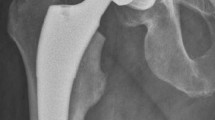

A total 123 patients who met the criteria were included in this study, their details were presented in Table 1. Apparently, we could find that there was a large drop in Hb of these elderly patients even before surgery (Fig. 1). We calculated details of their peri-operative blood loss to get conclusions which were described in Table 2.

It is obvious that the patients had a large drop in Hb before surgery and interference factors which could result in Hb decrease like hematopathy, laboratory results of bleeding disorders, taking drugs that possibly impact blood coagulation, gastrointestinal hemorrhage were also excluded. We hypothesized this drop could originate from the pre-operative HBL and attempt to quantify the HBL prior to the surgery.